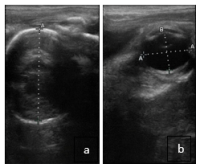

Between 9 and 11 months of gestation, the fetus typically settles into its final presentation. Using ultrasound, veterinarians can determine whether the foal is in a normal anterior presentation (head first). This is done by identifying the fetal head or eye.

If the fetus is in an abnormal position, such as posterior (hindquarters first) or transverse (sideways), the tail, thighs, or spine may be detected. Although fetal malpresentation is uncommon, it can lead to dystocia (difficult birth), posing serious risks to both mare and foal.